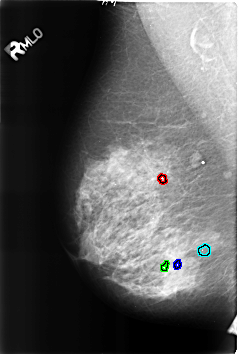

B_3227_1.RIGHT_MLO

FILE: B_3227_1.RIGHT_MLO.OVERLAY

TOTAL_ABNORMALITIES 4

ABNORMALITY 1

LESION_TYPE CALCIFICATION TYPE ROUND_AND_REGULAR-LUCENT_CENTER DISTRIBUTION N/A

ASSESSMENT 2

SUBTLETY 4

PATHOLOGY BENIGN_WITHOUT_CALLBACK

ABNORMALITY 2

ABNORMALITY 3

ABNORMALITY 4